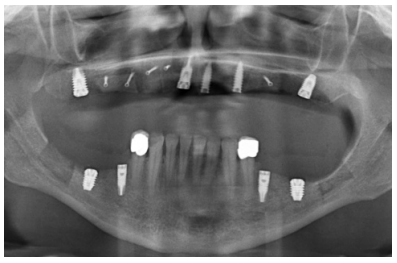

Para iniciar la fase de diagnóstico se realiza una radiografía panorámica que nos de una idea del estado general de ambos maxilares para iniciar el plan de tratamiento. En ella se ve como existe aparentemente altura en el reborde maxilar tanto a nivel anterior como posterior y un nervio dentario bajo en la mandíbula que nos permite tener una mayor cresta ósea residual disponible para la inserción de los implantes (Figura 3).

Cuatro meses después de la cirugía inicial de regeneración del maxilar se lleva a cabo un nuevo Cone-beam dental, en el que se planifica la siguiente fase de la cirugía en función de la ganancia ósea que se ha logrado con los injertos en bloque y la técnica de Split en dos fases. En las imágenes podemos observar como en las zonas de máxima atrofia, donde se colocan los bloques se ha logrado una anchura que triplica la inicial (Figuras 19 y 20). En la apertura del colgajo se observa como las imágenes del TAC de planificación se corresponden con la realidad, y además que la zona tratada mediante Split en dos fases ha logrado también una anchura de cresta que ahora permite la retirada de los implantes transicionales y la inserción de nuevos implantes en esta posición, con una mejor situación de partida y eje para la confección posterior de la prótesis (Figuras 21-22). Se procede a la inserción de los implantes y se realiza una prótesis provisional de carga progresiva apoyada en los implantes colocados en la primera fase quirúrgica. De este modo, la paciente puede tener una prótesis fija sobre implantes que servirá para ir dando forma a los provisionales en cuanto a estética y función de cara a la prótesis definitiva (Figuras 23-24).

Cuatro meses después se procede a la carga de los implantes insertados en esta segunda fase quirúrgica. De nuevo se opta por unas segundas prótesis provisionales de carga progresiva, elaboradas del mismo modo que las anteriores Tres meses después la oclusión está preparada para la confección de la prótesis definitiva, por lo que se transforma la prótesis en una prótesis metal-cerámica, atornillada sobre transepitelial confeccionada mediante cad-cam (Figuras 25-26). La paciente ha recuperado la función demandada, así como la corrección de la oclusión de la prótesis completa, que presentaba una mordida cruzada lateral derecha con disminución de la dimensión vertical al inicio del tratamiento. La paciente acude a sus revisiones y el tratamiento se mantiene estable tal como se muestra en las imágenes tomadas a los 10 años de seguimiento (Figuras 27-28).